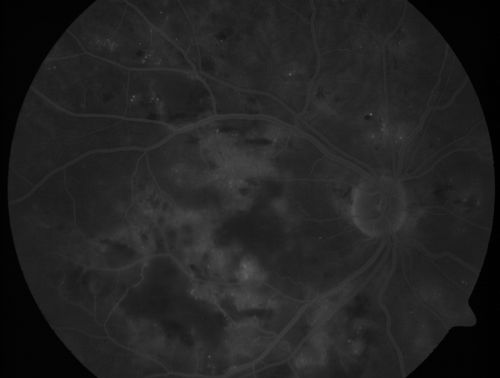

Diabetic Patient with Macular Edema and Blood Pressure 200/95

49-year-old decreasing vision over the last year. OD is 20/80, OS 20/80. blood pressure which was 200/95.

Hypertensive Retinopathy in a Diabetic

macular edema

cotton wool spots

diabetic

hypertensive